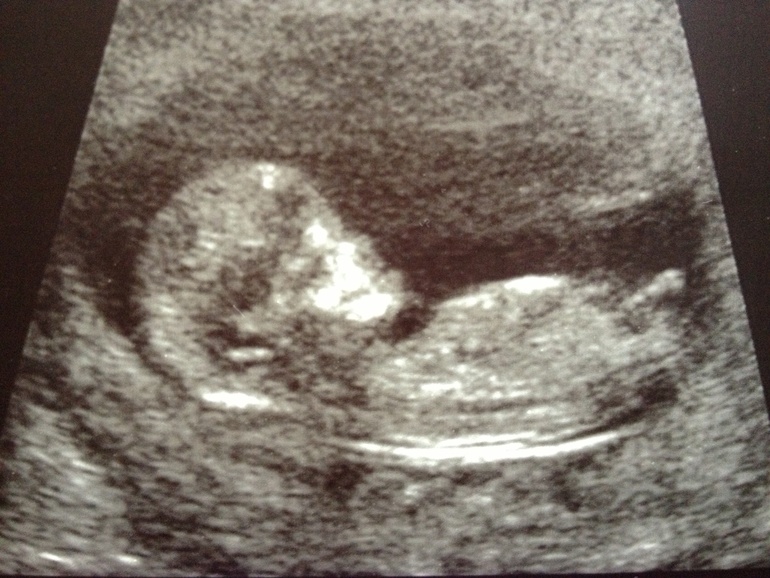

Вот мой малышочек в 11нед. и 6 дней, КТР 54мм!

на девочку похоже очень!)))недавно рассматривала, как различают пол на таком сроке по углу расположения половых органов)))у мальчиков больше вверх. а вот у девочек почти параллельно, примерно как у вас)))